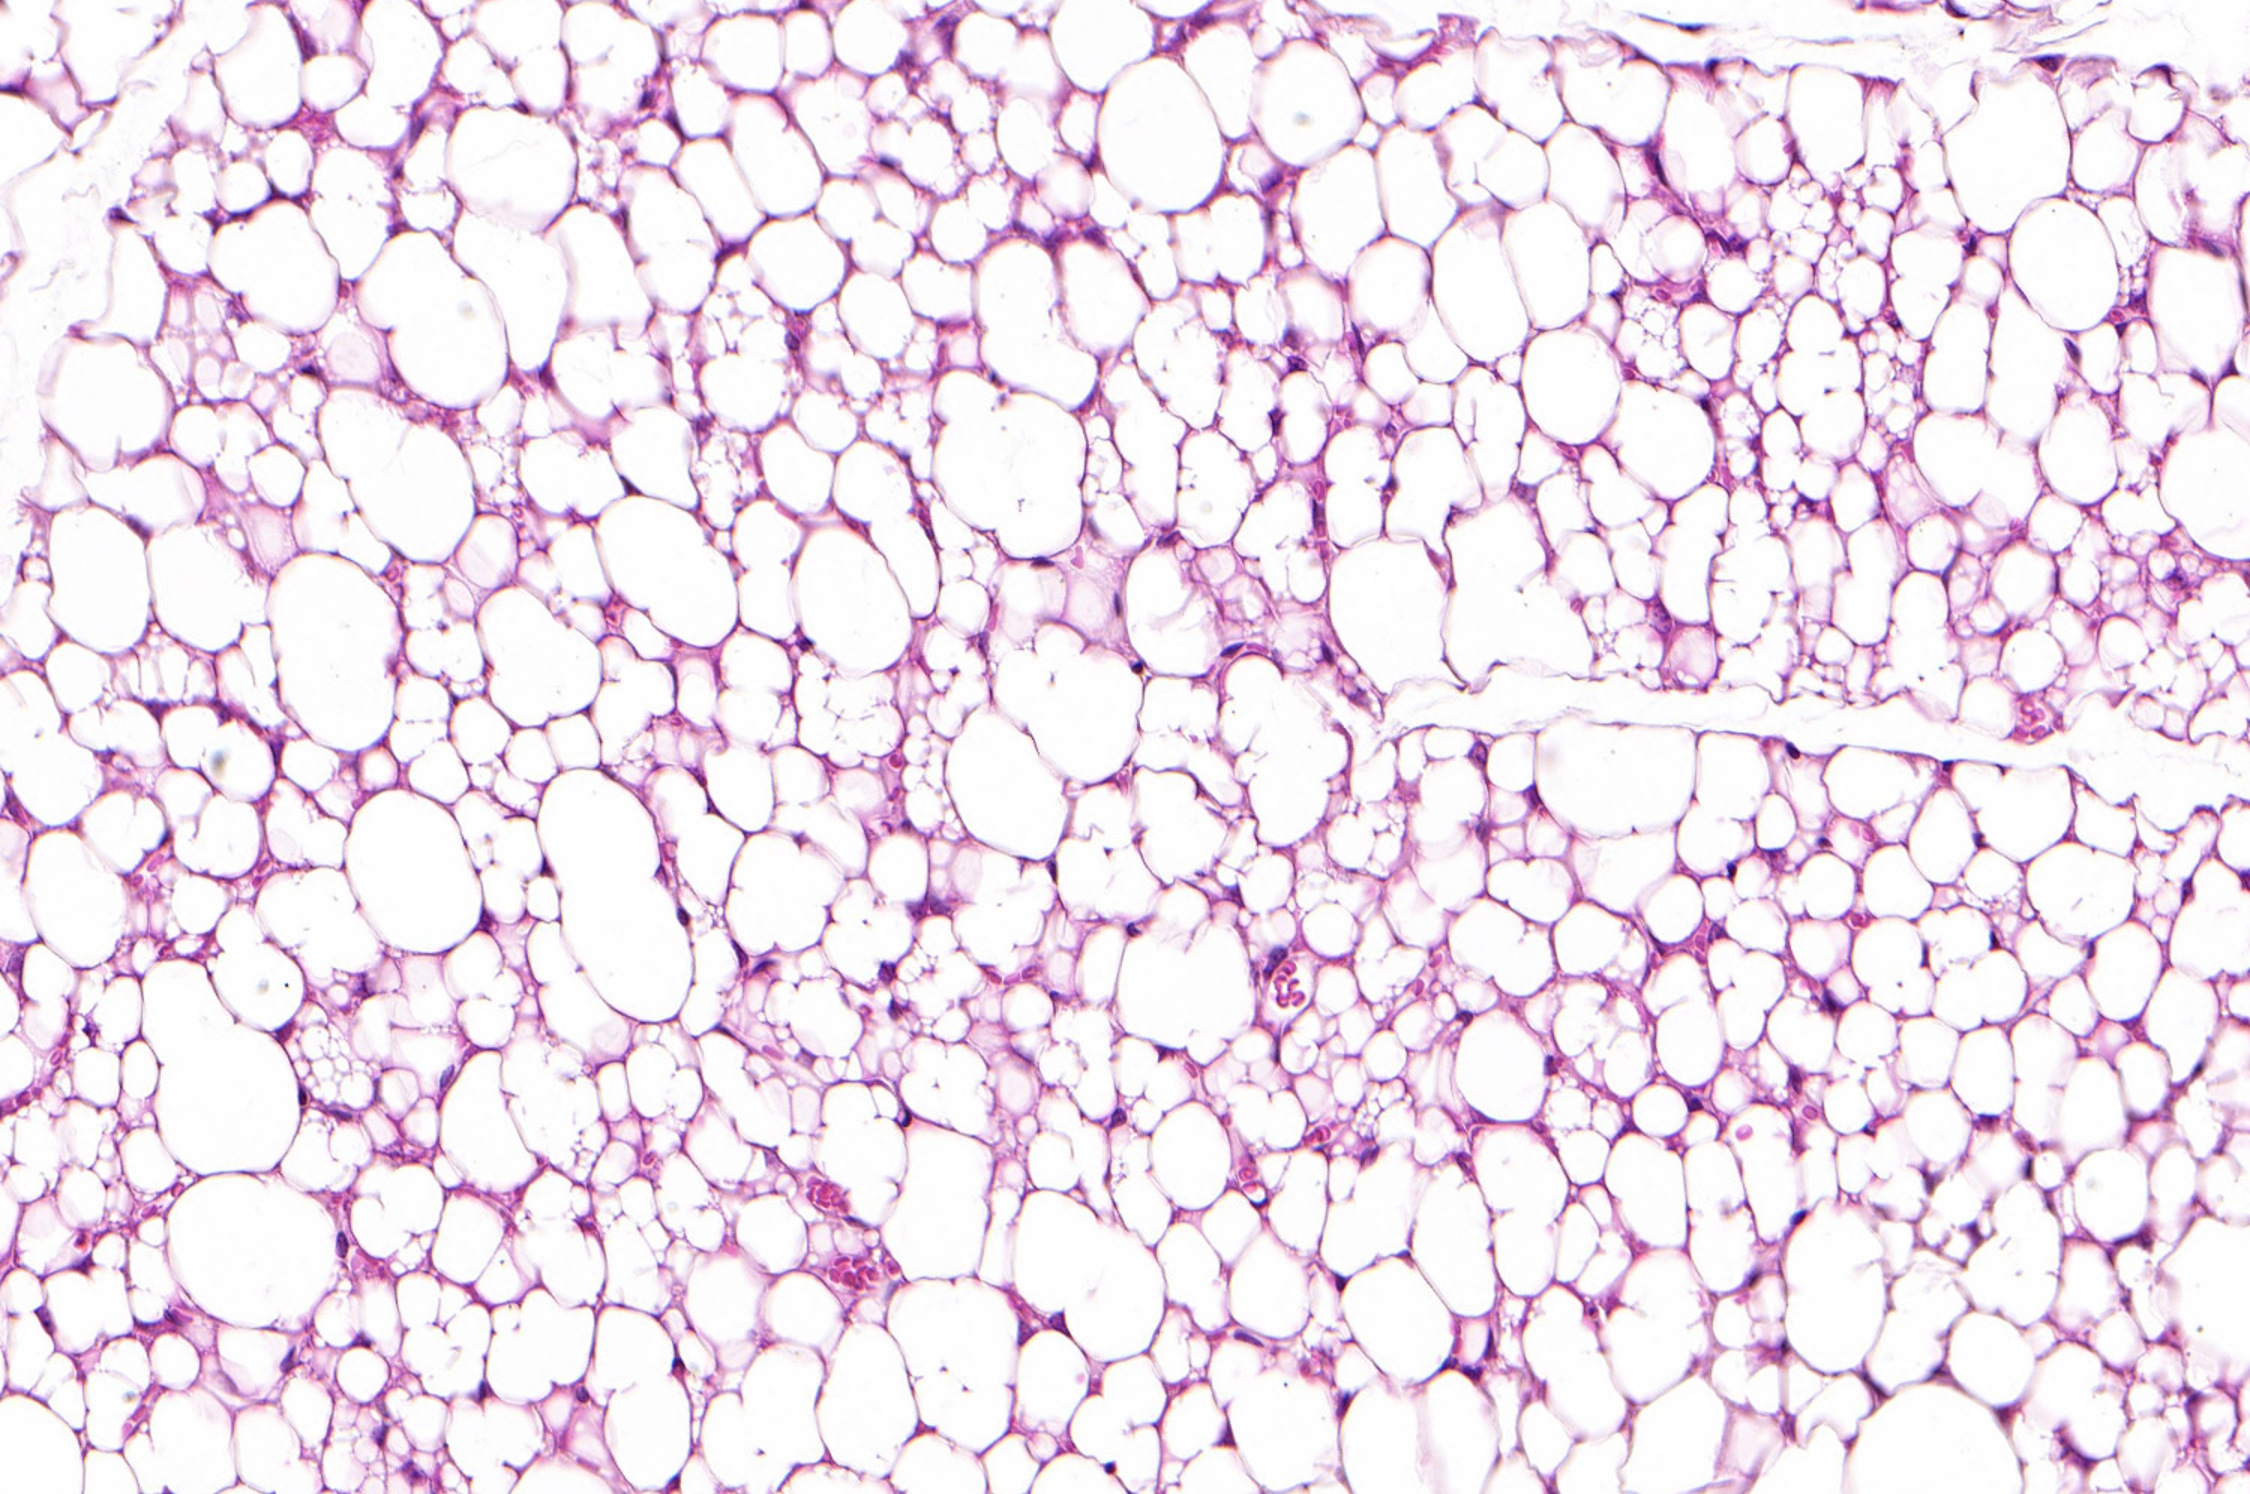

Weiß, braun, beige. Das sind die Farben der Fettzellen. Weiße Fettzellen speichern in unserem Körper Fett als Energiereserve. Wir brauchen diese Zellen. Zu viele davon wollen wir aber aus gesundheitlichen Gründen nicht. Die braunen Fettzellen sind vor allem bei Säuglingen aktiv. Sie produzieren Wärme und halten damit die Körpertemperatur der Babys aufrecht. Braunes Fettgewebe nimmt jedoch im Lauf des Lebens ab; Erwachsene haben nur noch sehr wenig davon.

Beige Fettzellen schließlich können ebenfalls Wärme produzieren, wenn auch etwas weniger gut als braune Fettzellen. Sie kommen auch bei Erwachsenen vor – eingestreut ins weiße Fettgewebe, vor allem im Nacken- und Schulterbereich. Sie helfen mit, überschüssige Energie zu verbrauchen.

Nun hat ein internationales Forschungsteam eine neue Art von beigen Fettzellen entdeckt und wissenschaftlich beschrieben. Diese unterscheiden sich von den bisher bekannten beigen Fettzellen. „Die neuartigen beigen Fettzellen spielen eine wichtige Rolle beim Energieumsatz im menschlichen Körper. Sie wirken positiv gegen Stoffwechselkrankheiten und Übergewicht“, sagt Anand Sharma, Studienautor der ETH Zürich.